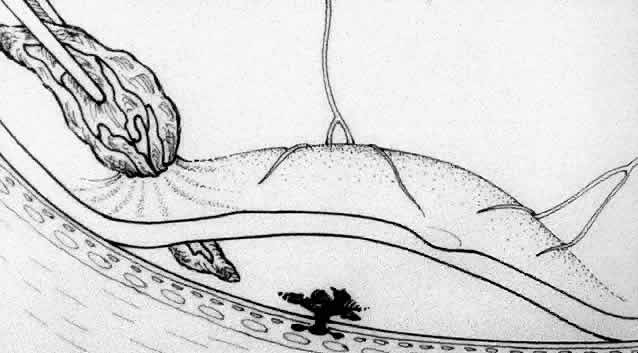

Besides being in the most advantageous location, the retinotomy should be as small as possible. Initially, we lightly diathermized the surface of the retina and then used the myringotomy blade to tease open a small hole through which an angled infusion needle was introduced.15 At the suggestion of Lambert and co-workers at Emory University, we stopped using diathermy. We now use a 120° angled, sharply pointed 36-gauge subretinal pick to pierce undiathermized neurosensory retina (Fig. 2). Occasional slight retinal hemorrhage can be controlled by transiently increasing the intraocular pressure. After the tiny hole has been made, the surgeon introduces the angled 33-gauge infusion needle beneath the retina and the assistant gently infuses balanced salt solution to elevate the neurosensory retina. This is accomplished by pushing on the plunger of a syringe that is connected to the hub of the needle by a short piece of tubing. As the fluid enters the subretinal space, attention is directed to edges of laser scars and/or adhesions to the underlying membrane (Fig. 3). Excessive infusion pressure can easily tear the retina. If areas of retina remain adherent, the infusion is stopped and the tip of an angled subretinal pick is carefully passed over the anterior surface of the membrane surface to break any residual adhesions. In a similar manner, the tip of the angled subretinal pick can be used to gently separate the thinned retina from an underlying photocoagulation scar. Occasionally, horizontal subretinal scissors are necessary to cut firm adhesions. These scissors have a similar 130° bend and blades approximately 3 mm in length to allow manipulation through an eccentric retinotomy. Trauma to foveal photoreceptors from either the pick or scissors is carefully avoided. If the retina is not mobilized over the entire photocoagulation scar, separation is achieved at least far enough into the scar to allow manipulation and extraction of the membrane without tearing the adjacent retina. The sharp tip of the angled subretinal pick is used to elevate the edge of the neovascular complex from the underlying RPE (Fig. 4). Care is taken to swing the pick in a pivoting or rotating manner to stretch or enlarge the retinotomy as little as possible. This requires close attention not only to the primary site of action at the membrane but also to the instrument shaft at the retinotomy site. In the appropriate cases, the complex dislodges easily from the underlying subfoveal RPE but remains attached to the edge of a laser scar (in recurrent cases) or to the stalk of choroidal vascular ingrowth.

We use positive action horizontal forceps that are angled 130° and have tips 3.2 mm in length.15 The tips are introduced (closed) through the retinotomy, which has usually enlarged slightly during the subretinal manipulation. The objective is to place the opened blades around the stalk or the adhesion, with the membrane in front of the blades. Gentle traction with the blades held closed breaks the connection (Fig. 5). This step is performed slowly and carefully. If traction on the retina is seen, the membrane is released and further separation of the complex from neurosensory retina is accomplished. If excessive tugging and displacement of surrounding RPE is seen, then consideration is given to using the subretinal scissors to cut the stalk rather than breaking it with the forceps. In virtually every case, the membrane (and often the adjacent laser scar) can be removed in one piece. As pathologic examination has confirmed, the abundance of cohesive basement membrane material matrix surrounding occasional capillaries, creates a complex of significant tensile strength.14